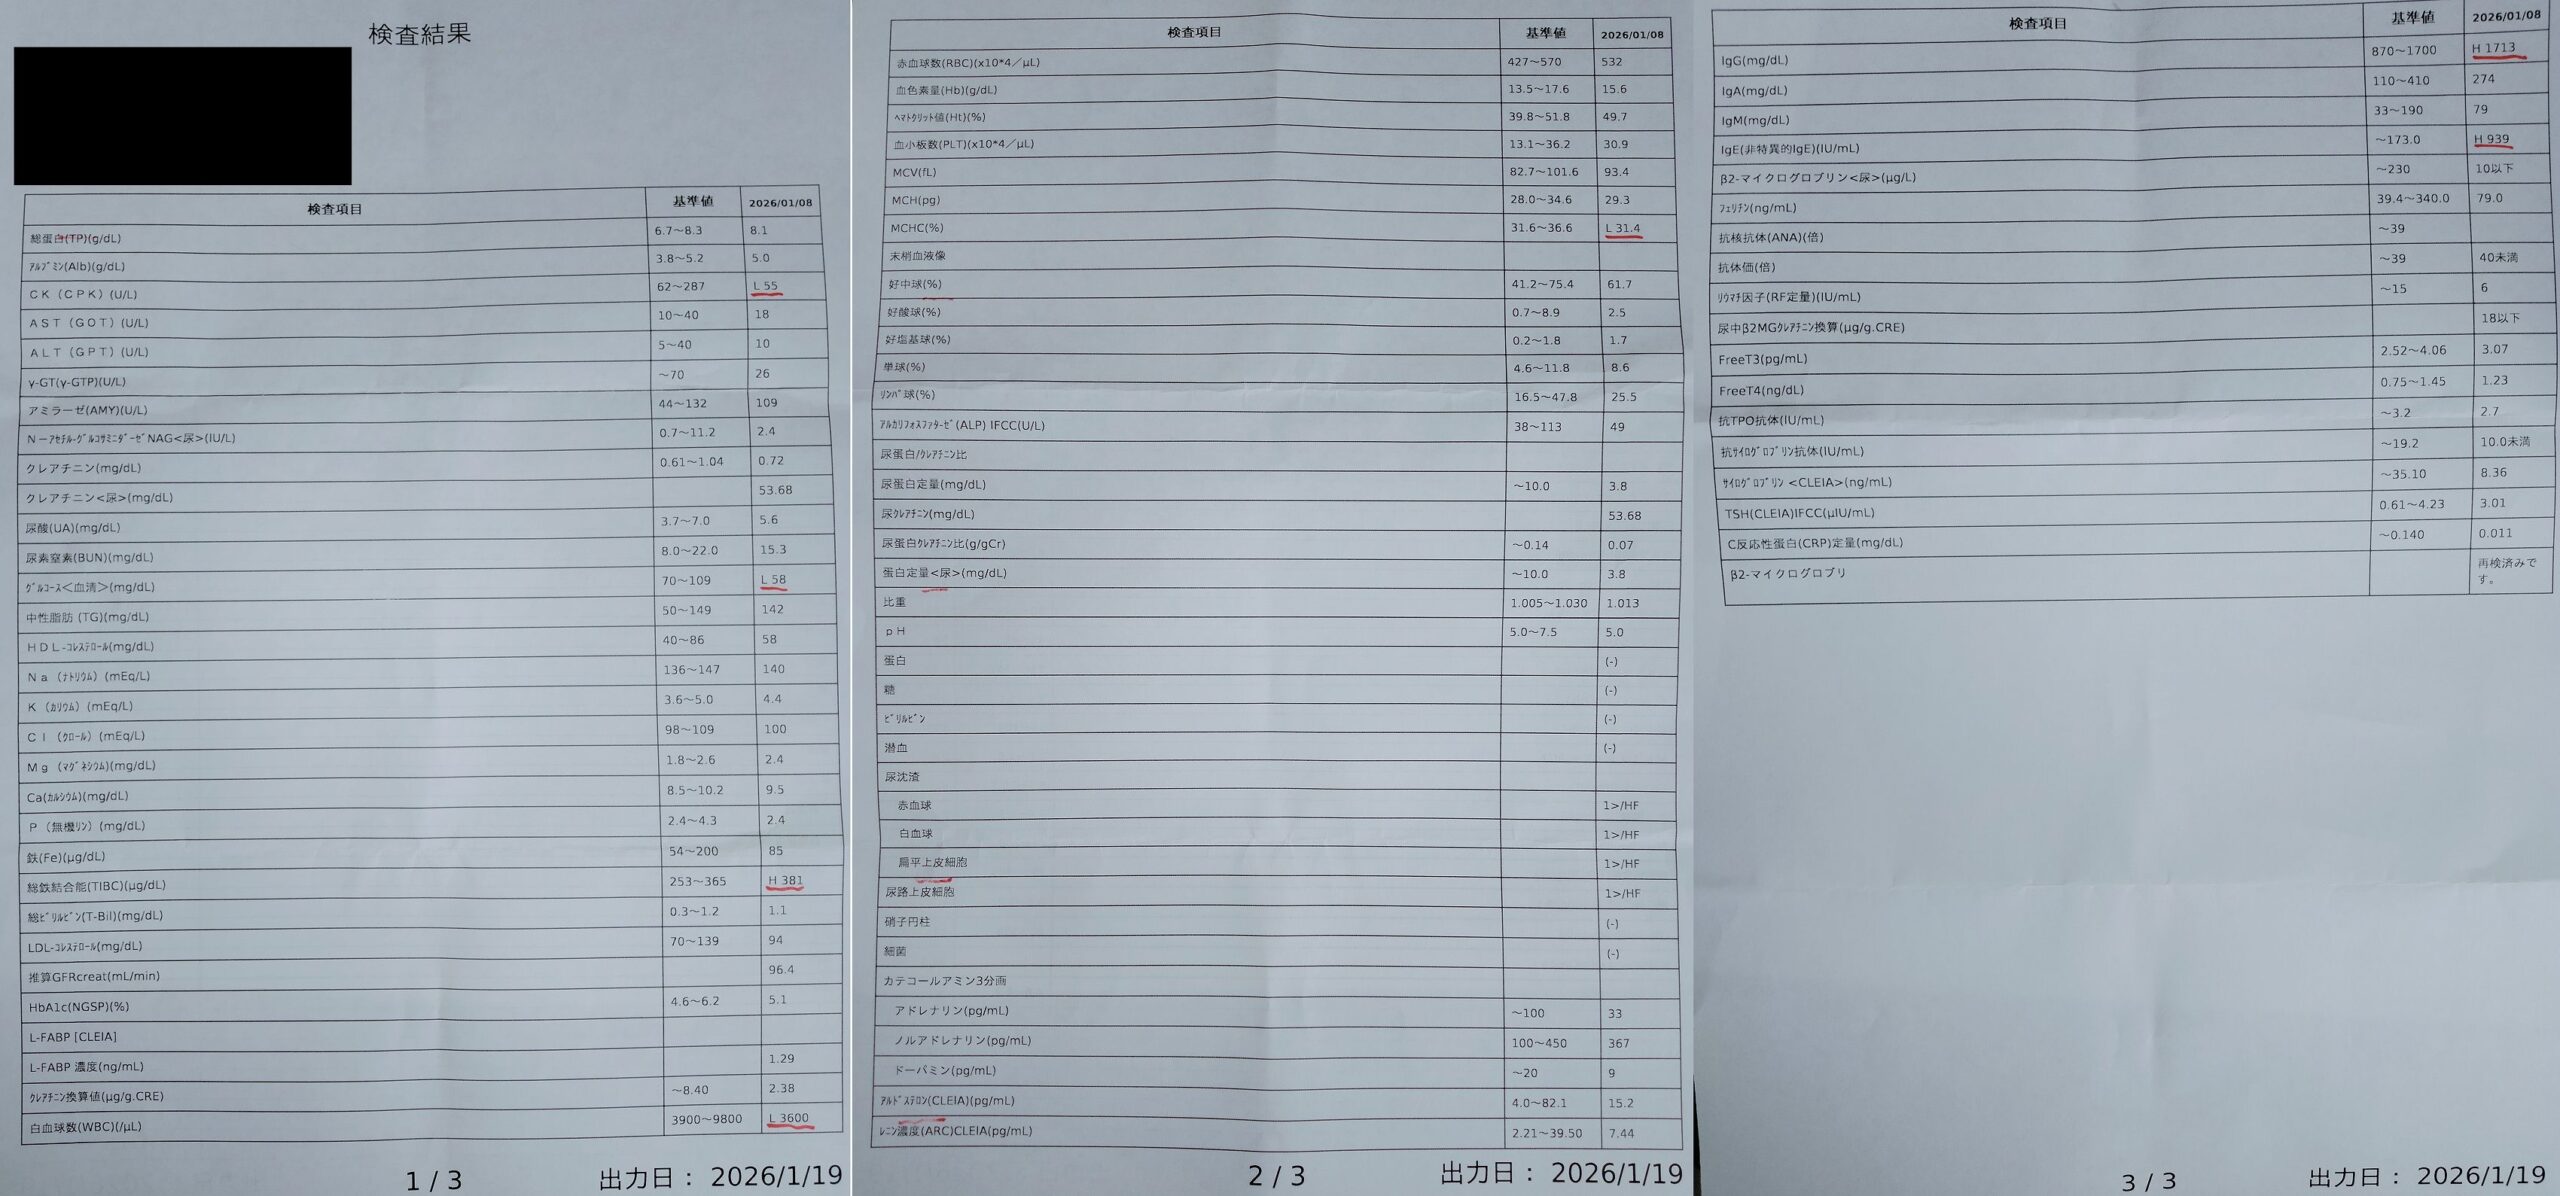

(血液検査の結果 2026/1)

↑甲状腺活動が活発になると「サイログロブリン<CLEIA>」が高くなる。この値含め、他の甲状腺値も全て正常なので悪性の疑いはなさそう。他の項目だと誤差範囲のずればかりで問題ない。IgE(非特異的IgE)が高くなっているが、これはアレルギー値で花粉症などで高くなる。